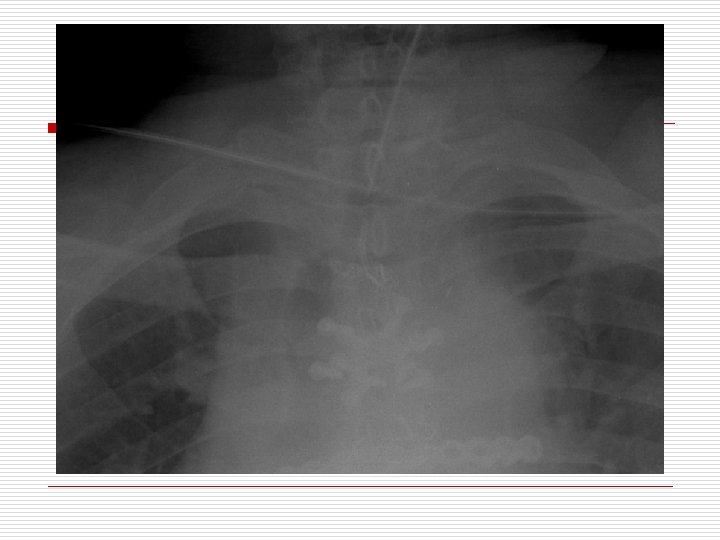

A 77 year old woman is brought to the ER for respiratory distress and emergently intubated. The ICU team is called due to hypoxia, tachycardia, and elevated airway pressures. Physical exam reveals harsh sounds on the right side with greatly decreased sounds on the left side.

A. B. C. D. The most appropriate treatment is: Needle decompression of the right side Needle decompression of the left side STAT Albuterol treatment Urgent CXR